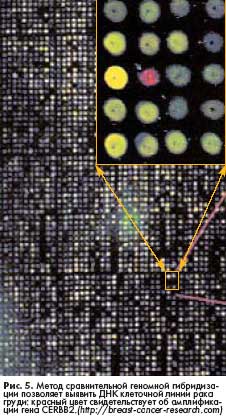

Говоря о новых методах диагностики рака груди, нельзя обойти вниманием достижения в области генетики. Так, например, молекулярные тесты, предложенные онкологами из University of Louisville (США), позволяют диагностировать агрессивные опухоли на ранних стадиях их развития. Метод разработан на основе ретроспективного исследования генов, активирующихся в клетках инвазивных форм рака груди. В ходе исследования ученые изучили 300 биоптатов, которые были законсервированы путем замораживания, что позволило сохранить структуру нуклеиновых кислот. При тщательном анализе ДНК были выявлены гены, экспрессия которых наблюдается в опухолевых клетках. Результаты еще одного геномного исследования позволяют достаточно точно определять вероятность рецидива рака у больных с впервые диагностированной опухолью груди без поражения лимфатических узлов. Методика предложена учеными из US National Surgical Adjuvant Breast and Bowel Project совместно со специалистами "Genomic Health", Inc.(США) и также основана на исследовании нуклеиновых кислот опухолевой ткани. При разработке метода ученые изучили хирургические образцы удаленных опухолей 668 пациенток, исходы лечения которых можно было проследить в течение длительного времени. В 2004 году компания "Genomic Health" представила клиническую лабораторную систему, созданную на основе полученных результатов и получившую название Oncotype DX™.